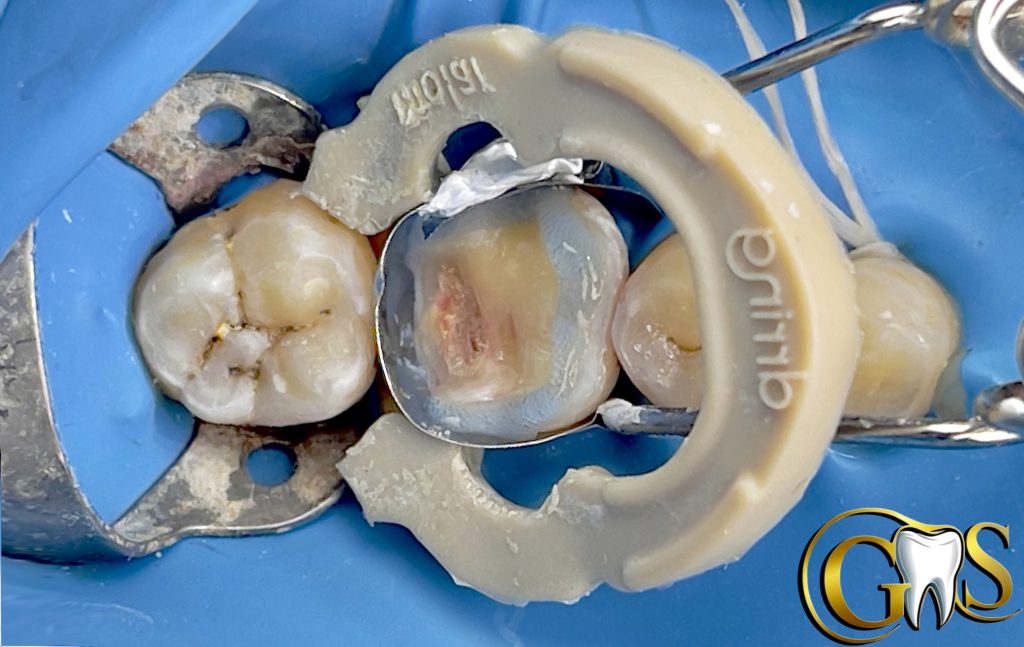

4-IDS

5-Resin coating

6-DWF (Decoupling with Fibers ) using Ribbond to improve Bonding with affected Dentine and for better stress Distribution

9-finishing and polishing